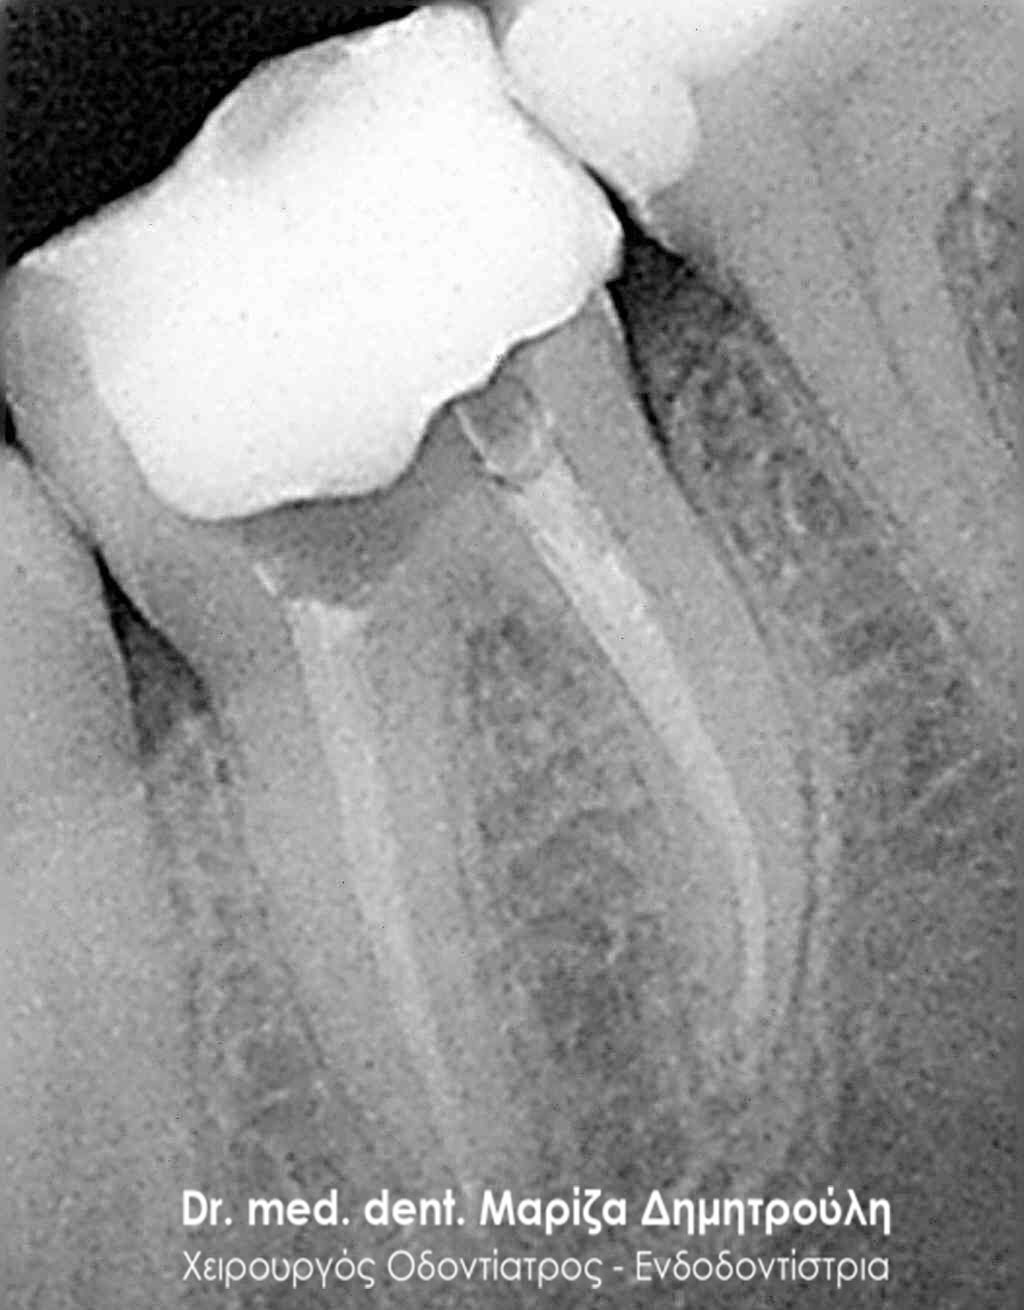

Πριν 2 χρόνια είχε πραγματοποιηθεί απονεύρωση στον πρώτο αριστερό μόνιμο γομφίο (τραπεζίτη). Ο ασθενής αναφέρει οτι από τότε που ξεκίνησε η ενδοδοντική θεραπεία, το δόντι δεν έπαψε ποτέ να πονάει.

Αρχικα ο ασθενής εξετάστηκε κλινικά και παρατηρήθηκε έντονος πόνος κατά την επίκρουση του δοντιού. Ακολούθησε ο ακτινογραφικός έλεγχος, ο οποίος εξήγησε και τα συμπτώματα πόνου του δοντιού. Διαπιστώθηκε οτι μόνο μία από τις τρείς ρίζες του δοντιού είχε εμφρακτικό υλικό. Η δεύτερη φαινόταν κενή, ενώ στην τρίτη διέκρινε κανείς μόνο την παρουσία κάποιου φυράματος.

Μετά την πλήρη ενημέρωση του ασθενή αποφασίστηκε η επανάληψη της ενδοδοντικής θεραπείας (απονέυρωσης) και η αποκατάσταση του δοντιού με καινούριο λευκό σφράγισμα.

Αρχικά στον ασθενή χορηγήθηκε τοπική αναισθησία και τοποθετήθηκε ελαστικός απομονωτήρας (λάστιχο). Στη συνέχεια πραγματοποιήθηκε διάνοιξη του δοντιού και αφαίρεθηκε το παλιό εμφρακτικό υλικό σε όλο το μήκος της ρίζας του δοντιού. Ακολούθησε η επεξεργασία του δοντιού με μηχανοκίνητα εργαλεία και οι διακλυσμοί ( έκπλυση ) στο εσωτερικό των ριζών για την απομάκρυνση των νεκρών οδοντικών ιστών / κυττάρων και την απολύμανση των ριζών. Έγινε τοποθέτηση φαρμάκου και έγινε προγραμματισμός για τη συνέχιση της απονεύρωσης σε επόμενο ραντεβού.

Εφόσον η ασθενής δεν πονούσε και το δόντι ήταν ασυμπτωματικό, ακολούθησε η ολοκλήρωση της απονεύρωσης με της έμφραξη των ριζών του δοντιού. Σε επόμενο ραντεβού το δόντι αποκαταστάθηκε με λευκό σφράγισμα.

ΠΡΙΝ

ΜΕΤΑ